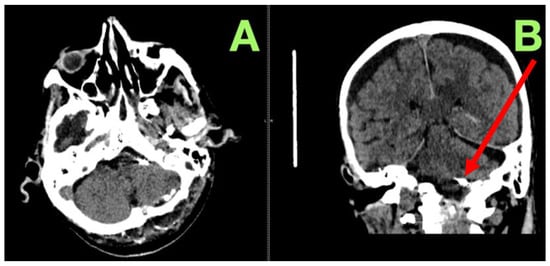

2. Case Presentation